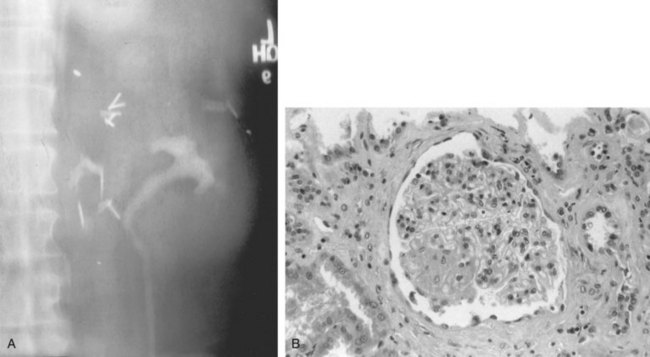

Patients who undergo nephron-sparing surgery for RCC may be left with a relatively small amount of renal tissue and are at risk for development of long-term renal functional impairment from hyperfiltration renal injury (Modlin and Novick, 2001; Abdi et al, 2003; Lane et al, 2009; Novick, 2009). In a study of 14 patients observed for up to 17 years after PN in a solitary kidney, patients with more than 50% reduction in overall renal mass were found to be at increased risk for development of proteinuria, focal segmental glomerulosclerosis, and progressive renal failure (Novick et al, 1990). The development of proteinuria correlated directly with the length of follow-up and inversely with the amount of remaining renal tissue. Renal biopsy revealed focal segmental glomerulosclerosis in several patients with severe proteinuria (Fig. 49–21). These findings mirror those observed in experimental animal models of partial renal ablation (Brenner, 1983). Because proteinuria is the initial manifestation of this phenomenon, a 24-hour urinary protein measurement should be obtained yearly in patients with a solitary remnant kidney to screen for hyperfiltration nephropathy.

Figure 49–21 A, Ten years after partial nephrectomy for large tumor in solitary left kidney, intravenous pyelogram shows function of small renal remnant. The patient had developed nephrotic syndrome at this time. B, Renal biopsy specimen shows focal segmental glomerulosclerosis indicative of hyperfiltration nephropathy.